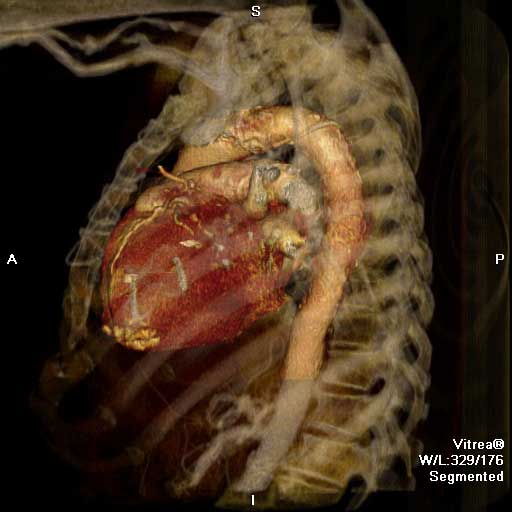

| Figure 1 & 2. Preoperative CT-scan | |

We report a case of a 78 y/o male with history of CAD, for which he underwent coronary artery by-pass surgery in 2004. The patient was admitted to the hospital with symptoms of moderate congestive heart failure. EKG showed no signs of acute ischemia and cardiac enzymes were negative. Cardiac ECHO showed a 6.8 x 5 cm pseudoaneurysm of the posterior left ventricle, well preserved ventricular function and no abnormalities of the mitral and aortic valves. Coronary angiogram demonstrated patency of all previous bypasses. The chest CT allowed better definition of the anatomy of the condition (Figure 1, 2). The procedure was performed through an antero-lateral left thoracotomy positioning the patient in a right lateral decubitus. The chest was entered at the 5th intercostal space and the sterno-costal junction was interrupted to optimize exposure. The left lung was displaced posteriorly and the pericardium was opened longitudinally and posteriorly to the phrenic nerve. Dissection of the heart surface from the pericardium was easily completed obtaining perfect exposure of the left ventricular pseudo-aneurysm. The previous by-pass grafts were never visualized, being distant from the operative field. Cardiopulmonary bypass was established through the left femoral vessels using a 17 F arterial femoral cannula and a 25 F multistage venous femoral cannula. The left ventricle was vented through the apex using a 10 F suction catheter. Systemic pressure was kept above 70 mmHg and the heart was decompressed before entering the left ventricular cavity via a longitudinal incision through the wall of the pseudoaneurysm (Figure 3). A bovine patch pericardial repair was completed with interrupted pledgetted sutures maintaining the architecture of the left ventricle (Figure 4). The closure was reinforced overlapping the wall of the pseudoaneurysm over the patch closure (Figure 5). Meticulous de-airing was completed under TTE monitoring before allowing ejection of the left ventricle into the circulation. De-airing was accomplished placing the patient in steep Trendelemburg position and maintaining full suction on the apical vent. Cardioplulmonary bypass was weaned-off without complications. The patient postoperative course was uncomplicated and he was discharged home in postoperative day 6. The postoperative CT-scan image is shown (Figure 6).